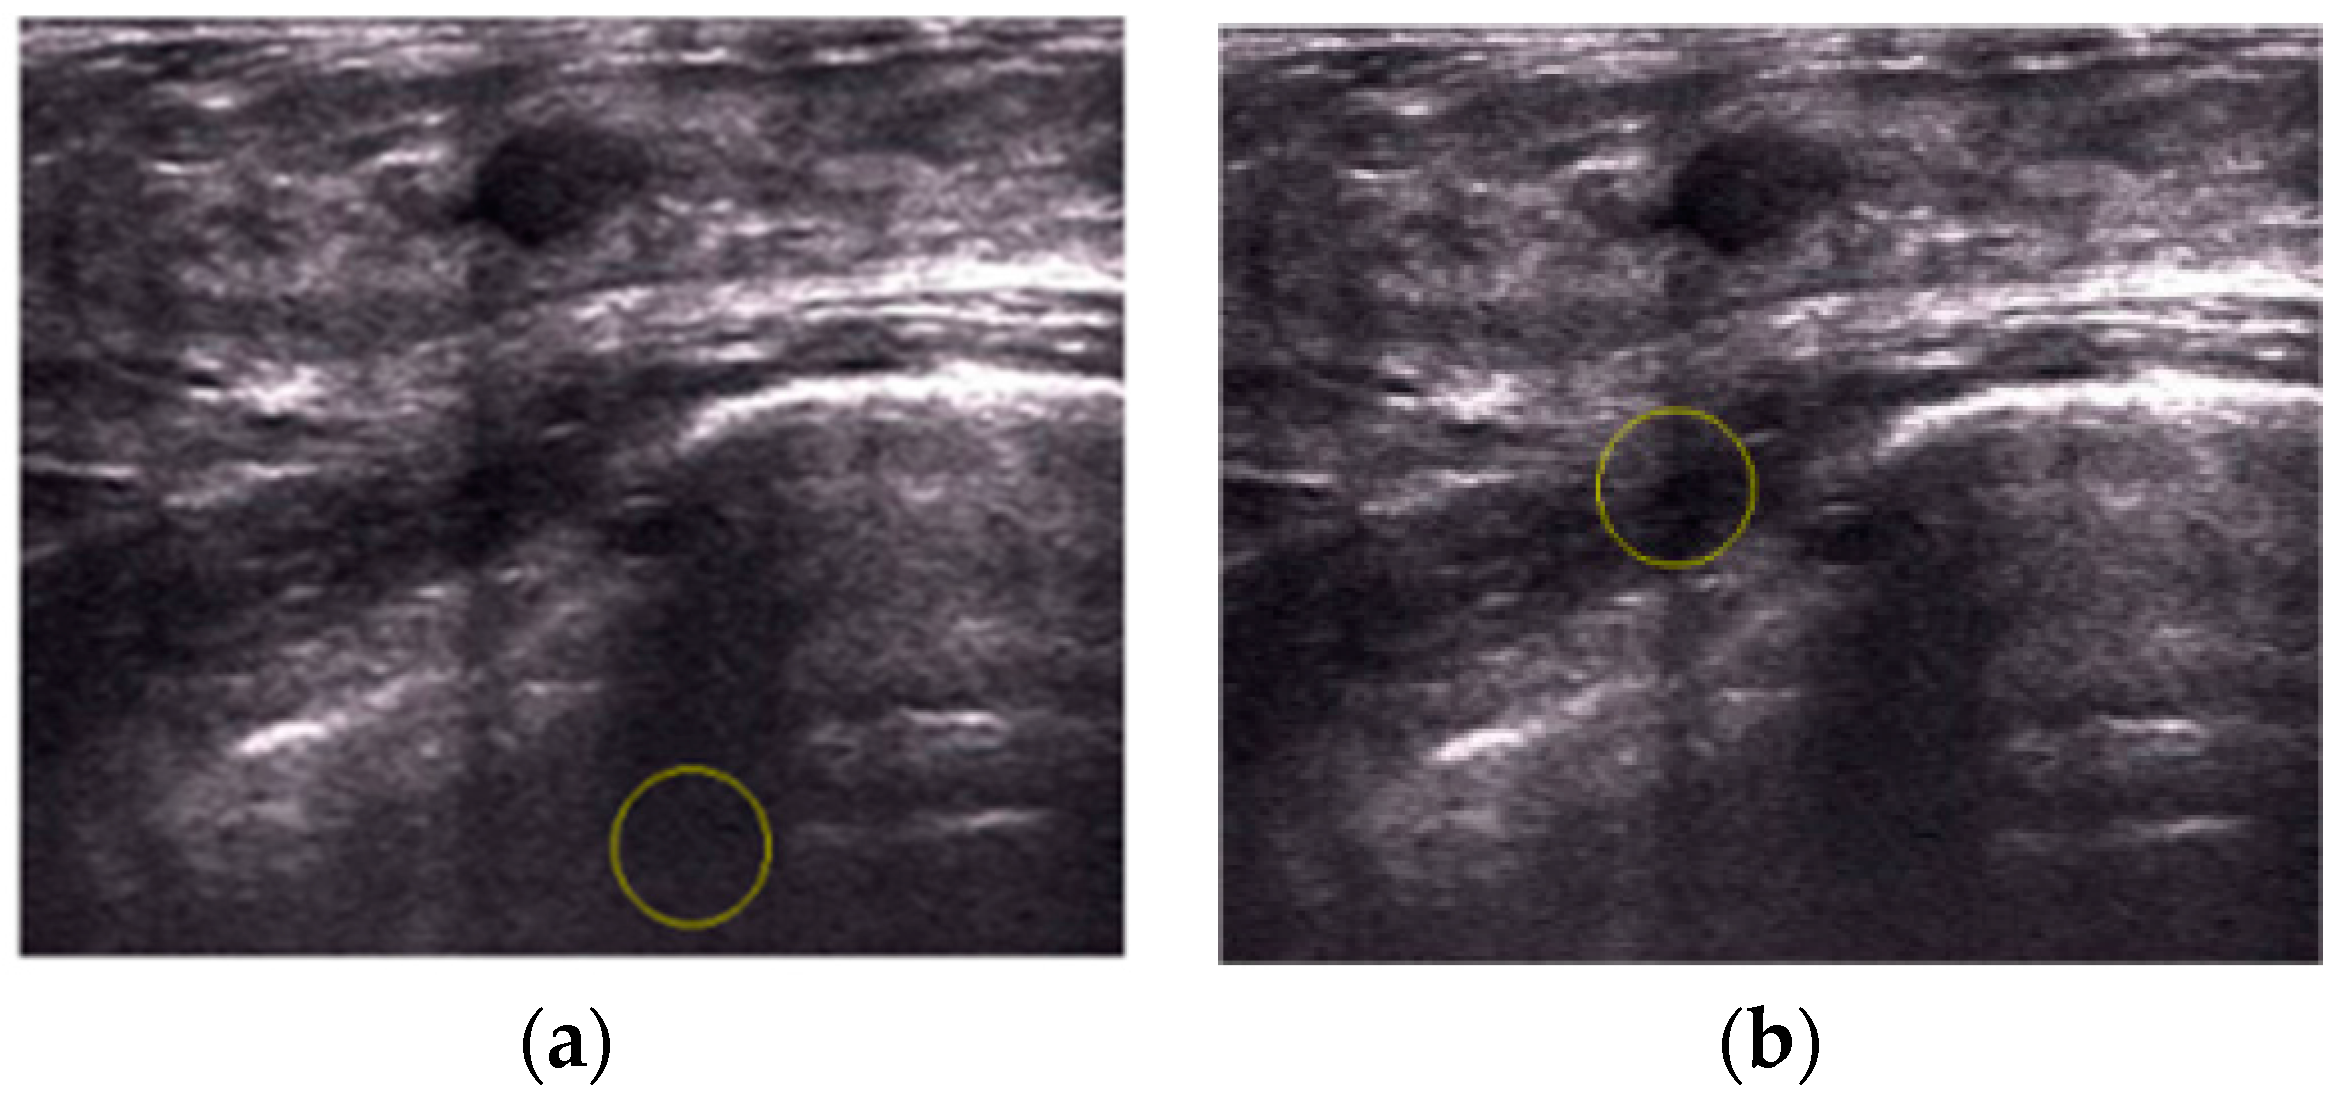

An Automatic Localization Algorithm for Ultrasound Breast Tumors Based on Human Visual Mechanism

Xie, Y.; Chen, K.; Lin, J. An Automatic Localization Algorithm for Ultrasound Breast Tumors Based on Human Visual Mechanism. Sensors 2017, 17, 1101. https://doi.org/10.3390/s17051101